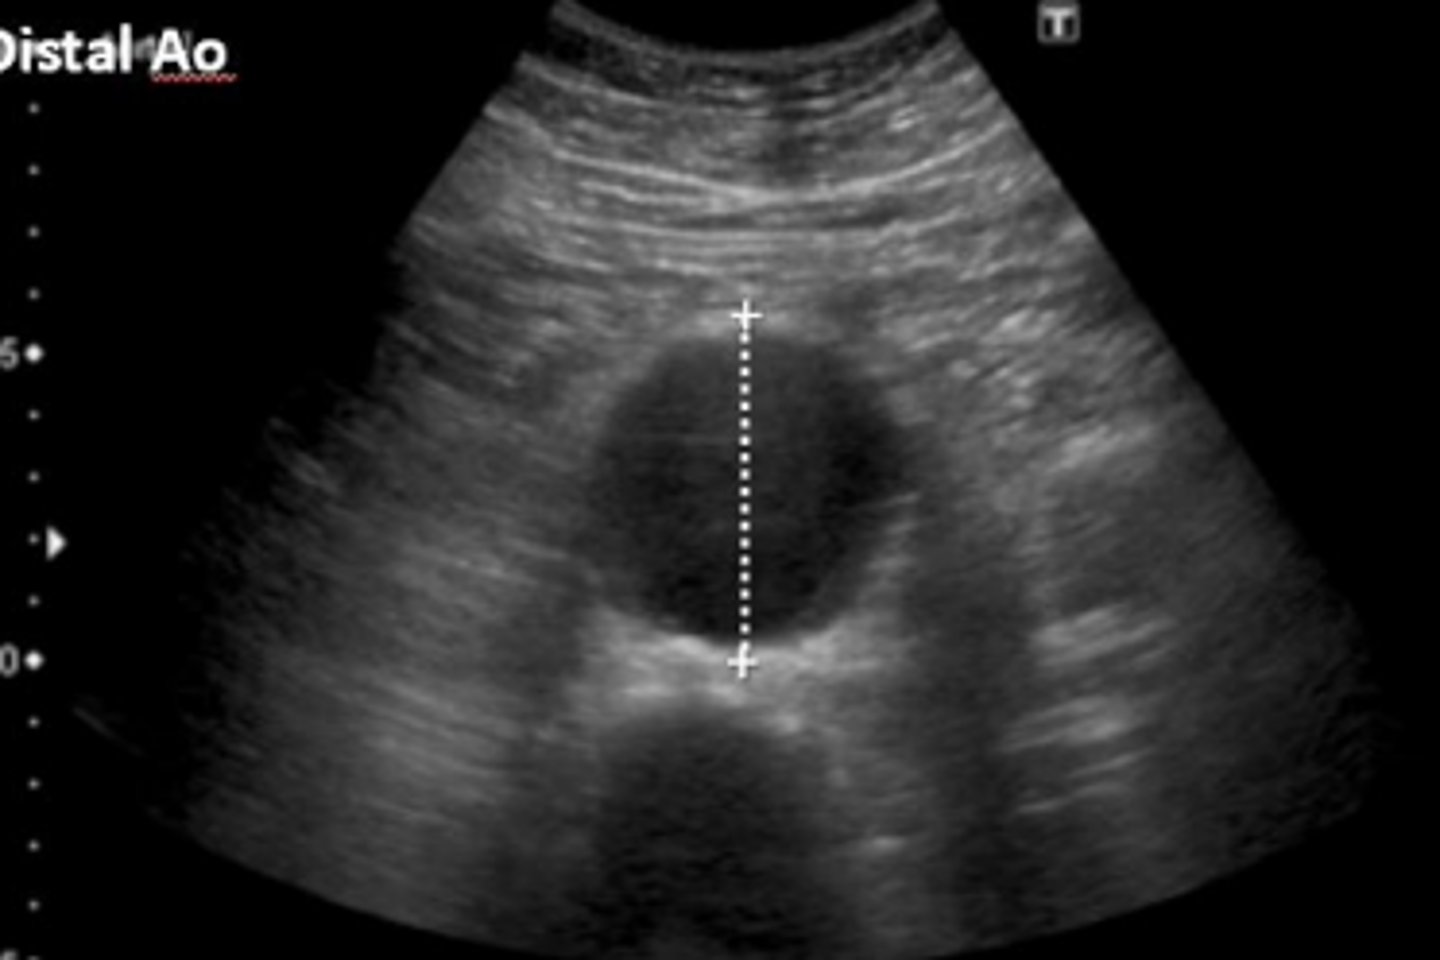

Abdominal aortic aneurysms (AAA) are most often _______ in location

fusiform

Abdominal aortic aneurysms (AAA) are most often _______ in morphology

>/= 3 cm

Abdominal aortic aneurysms are greater than ____ in diameter

distal aorta

Where do most AAAs occur?

AAA

What is seen here?

focal dilations of the aorta at least 50% larger than normal

AAAs are described as: